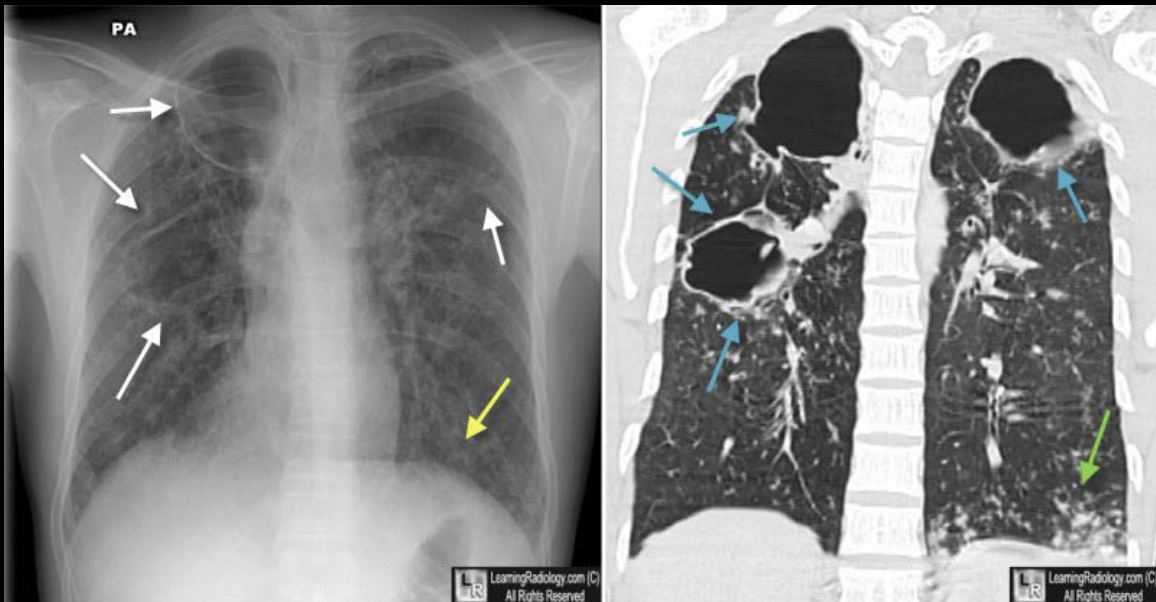

Nódulo solitario: primoinfección

Primoinfección